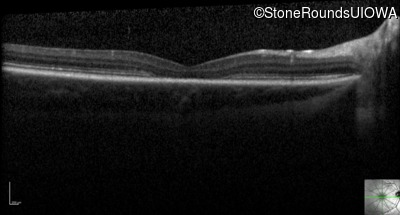

Optical Coherence Tomography - Left - 20/80

Exemplar / OCT Stack

OCT Stack